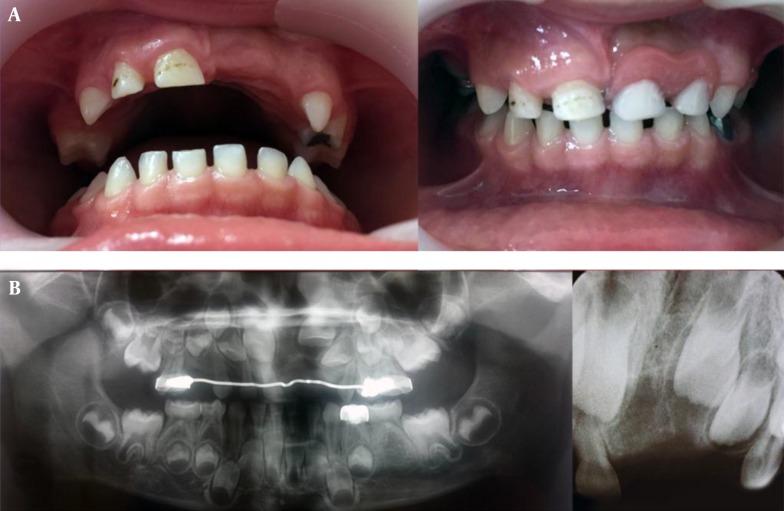

This is a case report of AFO accompanied with a number of impacted deciduous teeth and its management in a 4-year old boy. Examination of oral cavity revealed an extensive swelling from midline to left deciduous maxillary first molar, covered with normal mucosa. Radiographic examination showed a well-defined mixed radiolucent-radiopaque lesion that extended horizontally from midline to mesial border of the left maxillary primary first molar and vertically from alveolar crest to the floor of nose. The differential diagnosis was odontoma (ameloblastic fibro-odontoma, complex odontoma). Surgical enucleation and curettage was performed under general anesthesia. Histopathologic sections show bone trabeculae in marrow spaces. There was myxoid matrix in some spaces which contained odontogenic epithelial cells. These findings led to diagnosis of AFO. No sign of recurrence has been observed during the 12-month follow-up period.

本文报告一例4岁男孩的AFO病例,该病例伴有多颗乳牙阻生及其治疗情况。口腔检查发现,从正中线至左侧上颌乳中切牙有广泛肿胀,表面覆盖正常黏膜。影像学检查显示一个边界清晰的混合性透射线-阻射线病变,从正中线水平延伸至左侧上颌乳中切牙的近中边缘,从牙槽嵴垂直延伸至鼻底。鉴别诊断为牙瘤(成釉细胞纤维牙瘤、复合性牙瘤)。在全身麻醉下进行了手术摘除和刮治。组织病理学切片显示骨髓腔内有骨小梁。部分区域有黏液样基质,其中含有牙源性上皮细胞。这些发现确诊为AFO。在12个月的随访期内未观察到复发迹象。